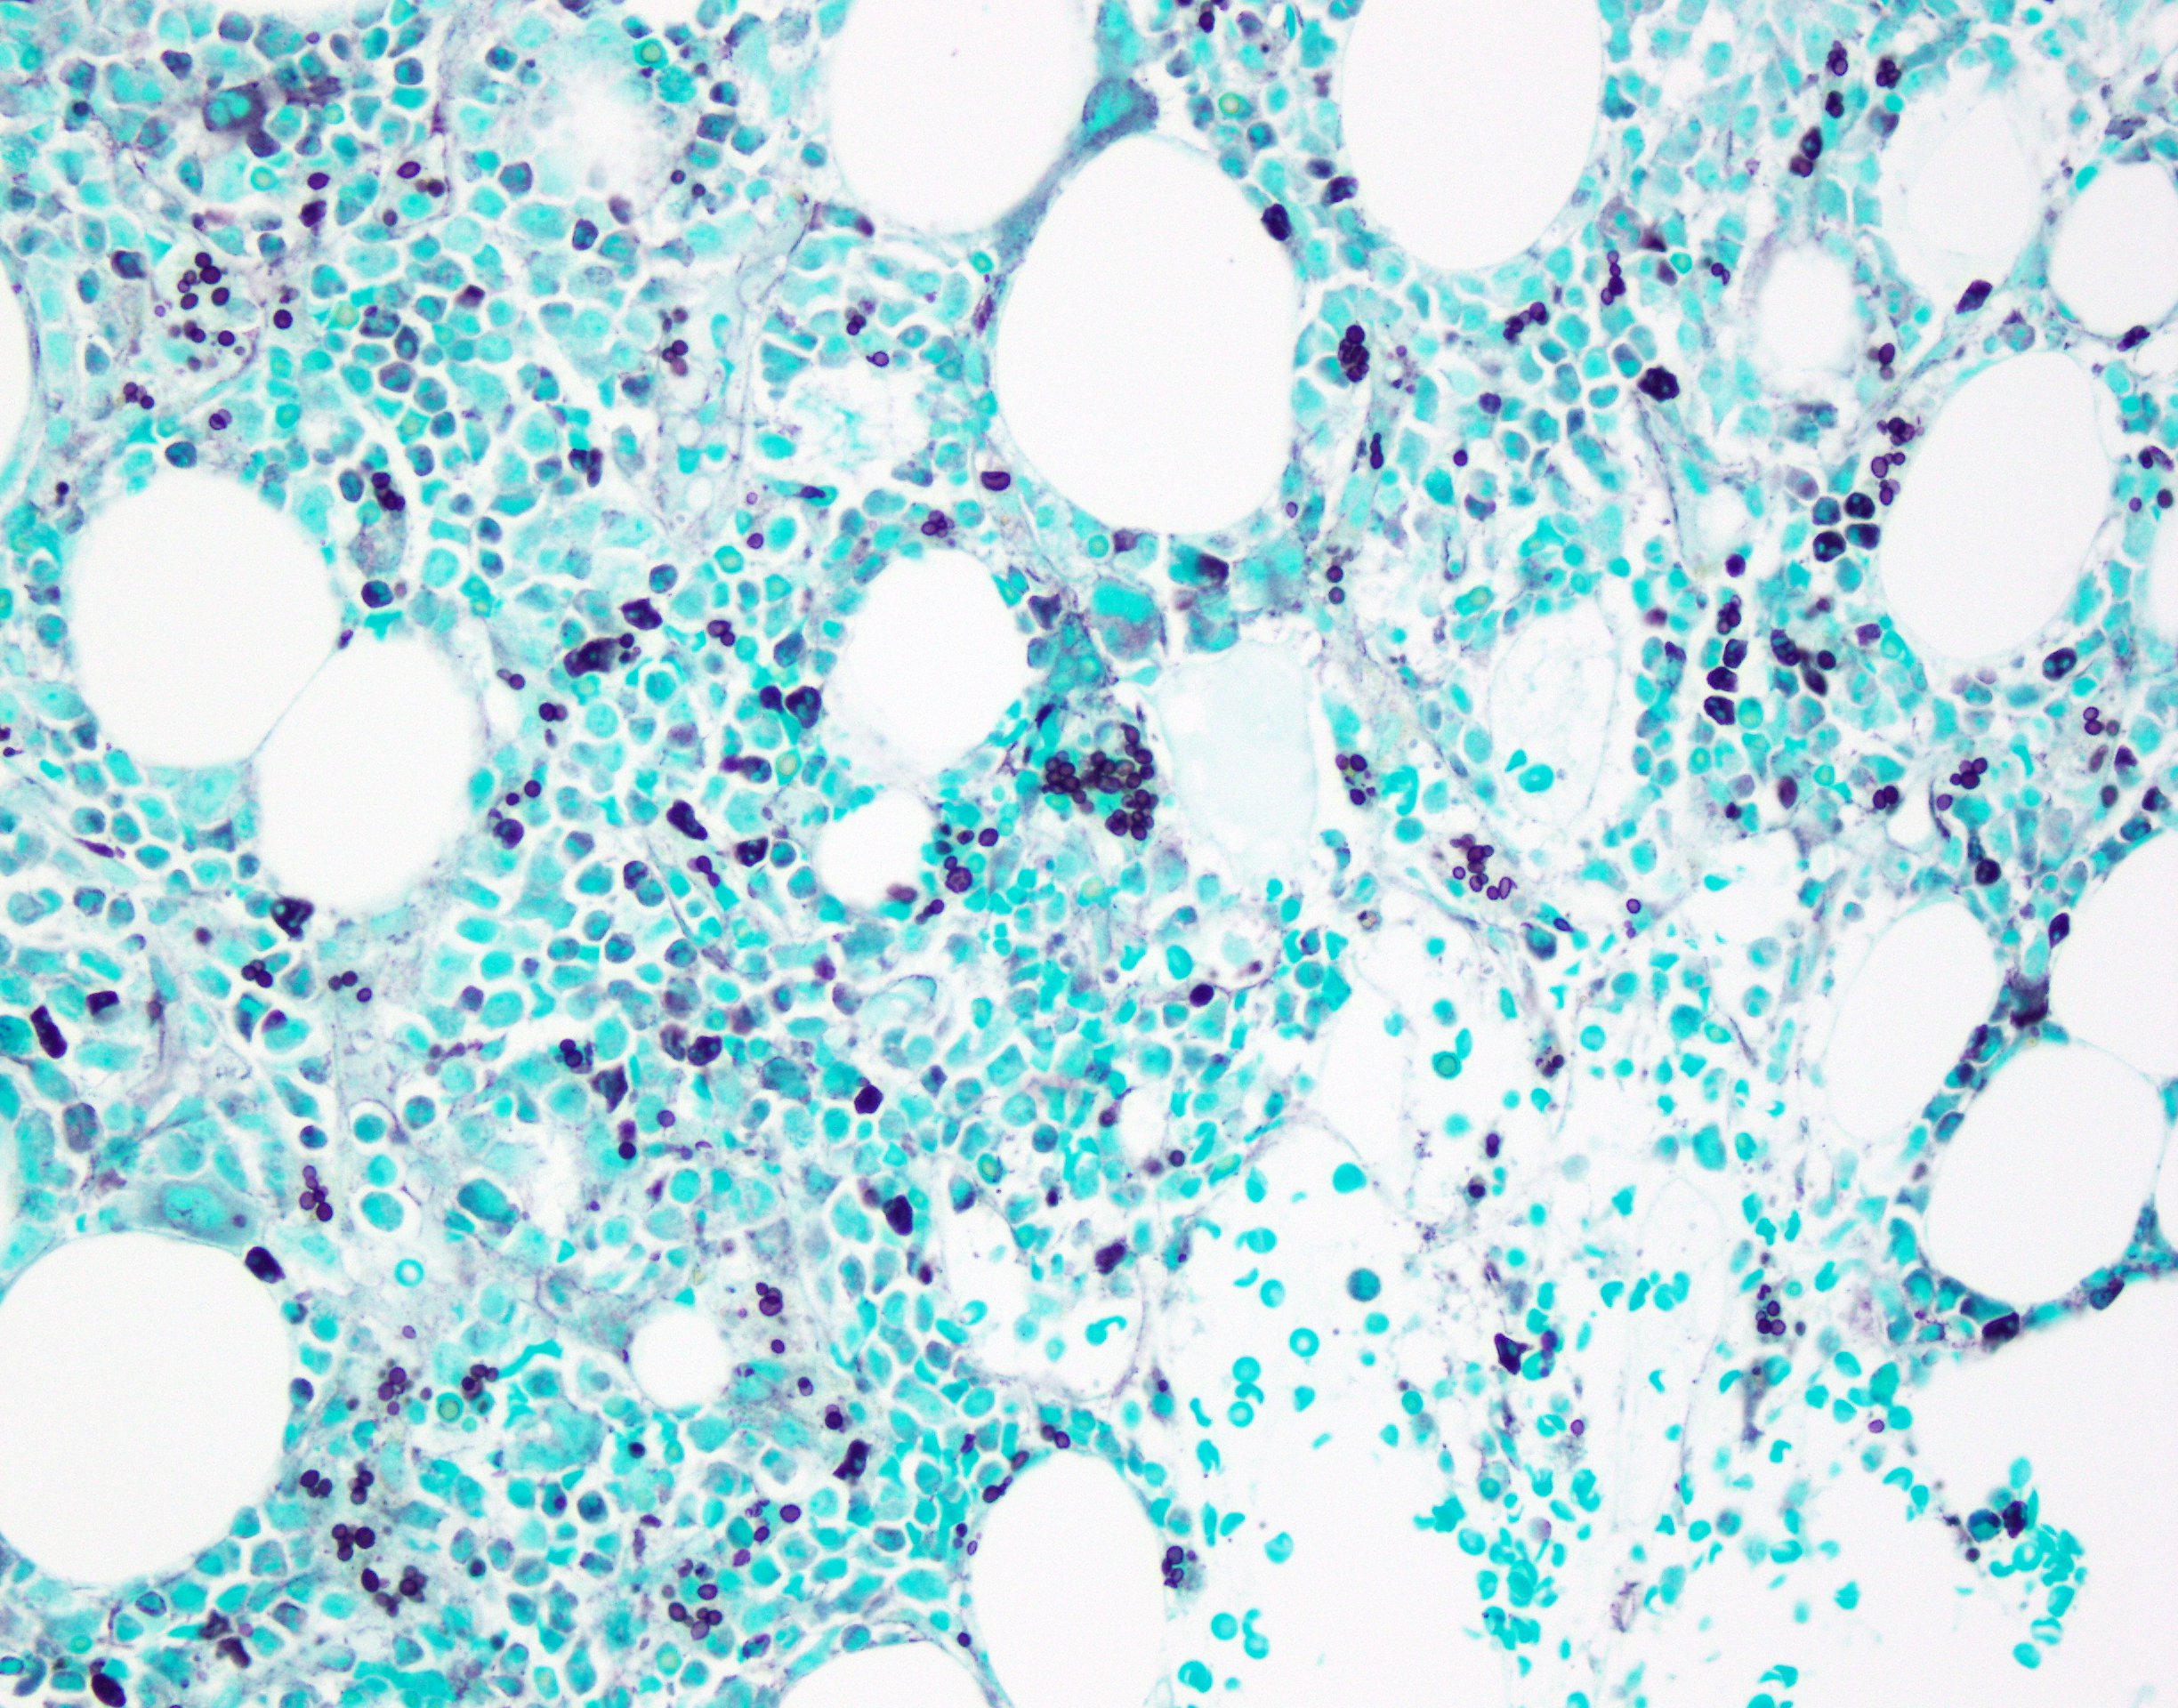

Case Presentation: A 44 year-old man who resides in Alexandria, LA presented via air ambulance from Honduras with three weeks of fever, night sweats, and right upper quadrant abdominal pain. He had associated nausea, vomiting, diarrhea, and headache. Exam was notable for fever and hepatomegaly. Serum studies revealed a creatinine of 6 mg/dL, elevated AST, ALT, alkaline phosphatase and GGT, as well as a microcytic anemia and thrombocytopenia. A 4th generation HIV test returned positive. CD4+ count was 7/mm3. HIV viral load was >10 million copies/mL. Acute viral hepatitis serologies and T-SPOT were negative. Lumbar puncture was performed with unremarkable CSF studies and a negative CSF cryptococcal antigen. Abdominal CT displayed only splenomegaly. Ferritin was >15,000 ng/mL and fasting triglycerides were elevated. A urine histoplasma antigen returned positive. Bone marrow biopsy revealed no malignancy but showed hemophagocytic histiocytes and numerous intracellular yeast forms compatible with Histoplasma spp. Renal biopsy exhibited budding yeast in the interstitium with associated acute and chronic inflammation and tubuloepithelial injury. Serum soluble IL-2 was within normal limits and NK cell function was borderline elevated. Routine and AFB blood cultures and CSF cultures were sterile. In addition to starting abacavir/lamivudine and dolutegravir, the patient was treated with liposomal amphotericin B induction for two weeks before transitioning to oral itraconazole. Three months after discharge he remains in care with evidence of renal recovery.